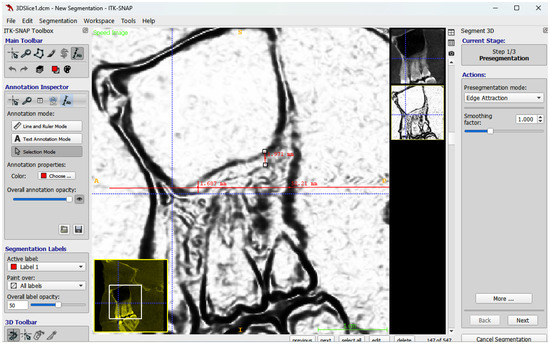

Background/Objectives: The aim of this study was to compare two methods for maxillary sinus volume measurement, assessing their accuracy. The analysis compared the maxillary sinus volume in patients with unilateral cleft lip and palate (UCLP) and in a non-cleft group, using a manual method and a three-dimensional (3D) semi-automated segmentation method. Methods: The research was conducted according to the STROBE guidelines. Sixty patients were included in this study: thirty patients with UCLP were in the research group, and the control group consisted of 30 patients with no craniofacial deformities. Cone-beam computed tomography (CBCT) was analyzed. The manual maxillary sinus volume was calculated based on its approximation to two geometric shapes based on mathematical formulas using linear measurements that were performed on all sinus CBCT scans in the maximum diameter in three planes. The semi-automatic segmentation method using ITK-SNAP 3D-imaging software version 4.2.2 was used to automatically calculate the maxillary sinus volume of the sinuses. The manually calculated volume was compared with the automatically calculated one, and statistical analysis was performed. Results: The cleft group presented lower values in both the automatic and manually calculated volumes for both the right (automatic: p = 0.49; manual p = 0.009) and left (automatic: p = 0.46; manual p = 0.11) maxillary sinuses than the non-cleft group. The cleft group presented statistically significant higher discrepancies in values between the manual and semi-automatic method than the control group (RMSV p = 0.0011; LMSV p = 0.033; TMSV p = 0.003). Conclusions: The manual method may not reveal the exact anatomical topography of the maxillary sinuses. In UCLP patients, the maxillary sinus anatomy may be more complex. Therefore, a semi-automated method may be more advisable to preserve the accuracy of the measurements. Full article

Show Figures

Figure 1